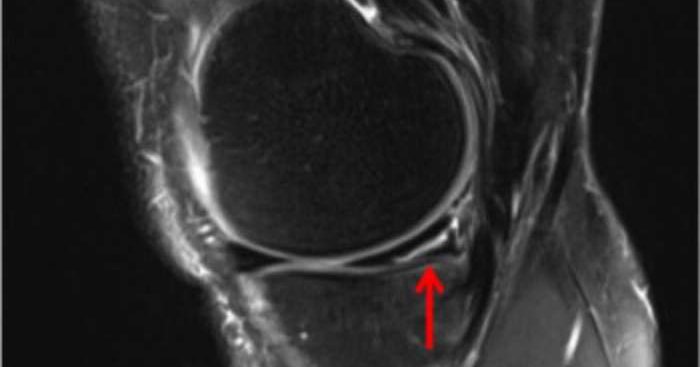

#Osteochondritis #dissecans (#OCD) of the knee is diagnosed through exam & imaging. Patients often have pinpoint joint line or kneecap pain. X-rays and #MRI help detect lesions, loose fragments, cysts, and healing potential, especially in younger patients.

Osteochondritis dissecans knee can affect any joint in the body, but the knee is the most commonly affected joint.